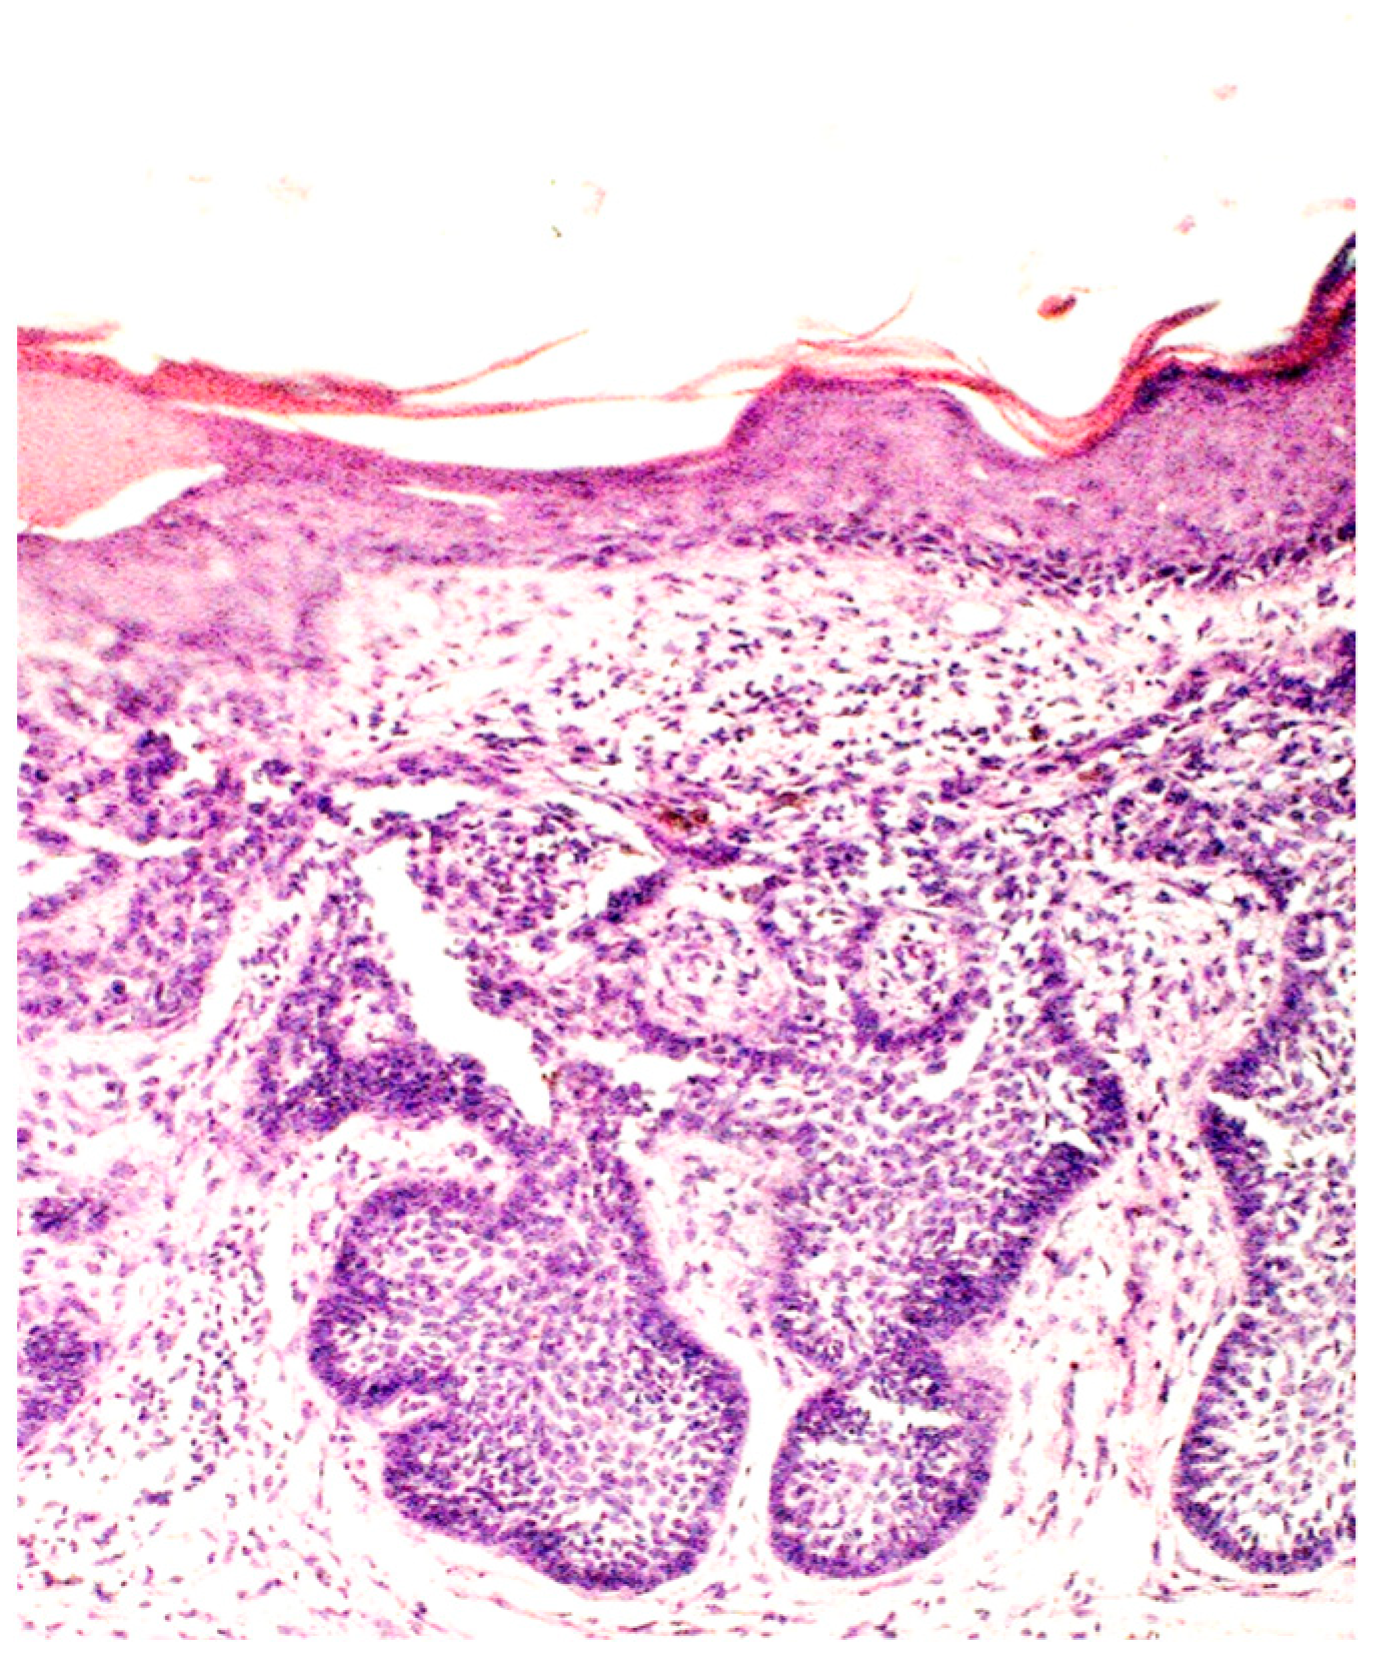

Figure 3.

Basaloid nest accompanied by collagenous scar tissue and elastosis (H&E; original magnification ×100).

BCC histopathological subtypes are categorized based on their proclivity for tumor recurrence. The subtypes with a lower risk of recurrence include nodular, superficial, pigmented, infundibulocystic, and fibroepithelial variants. Conversely, those with a higher risk of recurrence encompass micronodular, infiltrating, morpheaform, and basosquamous types [10,79,80]. Unfortunately, there is a lack of histological descriptions in the literature specifically addressing BCC development in scar tissue. Still, morpheaform basal cell carcinoma, which is the most common variant of BCC occurring within scar tissue, is characterized by the presence of tumor cell strands that are intricately embedded within a densely fibrous stroma [3]. The tumor cells are closely arranged in columnar formations, which can sometimes be as slender as one to two cells in width, all surrounded by collagen-rich fibrous stromal tissue. [81,82]

From clinical case reports, it is known that the histological examination of BCC developing on a scar post-BCG vaccination can reveal distinct features. Histological analysis may show an ulcerated multifocal BCC with a small granuloma in the subjacent dermis [42]. Another example includes histological findings of nests of basaloid cells with peripheral palisading and absent granulomatous infiltrate, confirming the diagnosis of nodular BCC [30]. Additionally, histology may reveal signs of collagenous scar tissue with retraction spaces and elastosis, along with atypical basal cells with peripheral palisading beneath the epidermis, consistent with a superficial BCC [31].